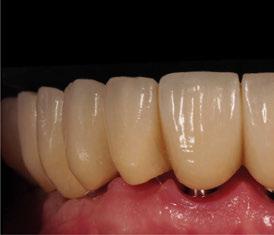

directamente a cabeza de implante para realizar una prótesis dentoalveolar de cerámica de 3 piezas, que equilibraran la oclusión y dieran soporte al labio y la mejilla (Figuras 14-17)

Figura 14. Imagen intraoral frontal postoperatoria al año de la reconstrucción.

Figura 15. Detalle de prótesis dentoalveolar cerámica en visión lateral.